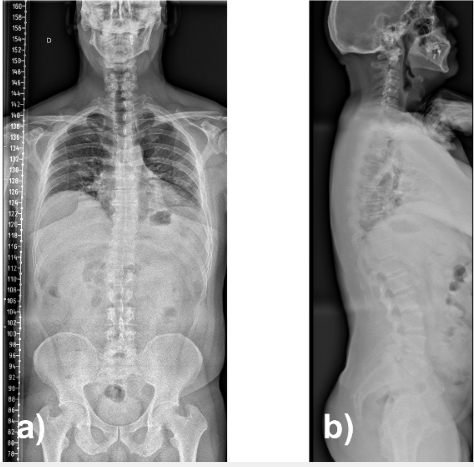

Dynamic radiographs confirmed a stable grade I lytic anterolisthesis at L5–S1 and mild degenerative retrolisthesis at L4–L5 (Fig. 2). Full-spine standing radiographs showed pelvic incidence 70°, lumbar lordosis 68°, segmental lordosis L4–S1 42°, sacral slope 48°, thoracic kyphosis 45°, and sagittal vertical axis −12 mm, consistent with globally compensated sagittal alignment (Fig. 3).

Figure 3: Full-spine radiographs in anteroposterior (a) and lateral (b) projections.